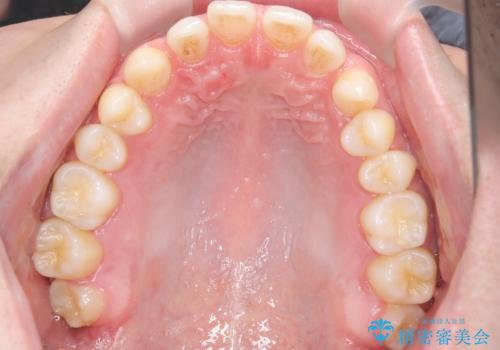

- 主訴:上の歯列の空隙を閉じたい

上顎前歯部に空隙が目立ちました。ワイヤー矯正、インビザライン(マウスピース矯正)どちらの方法でも適用症例と説明し、ワイヤー矯正治療(審美装置)を希望されました。

上顎歯列の空隙を閉じるのと一緒に、ディープバイト気味の被蓋も下顎前歯の圧下を行い改善しました。